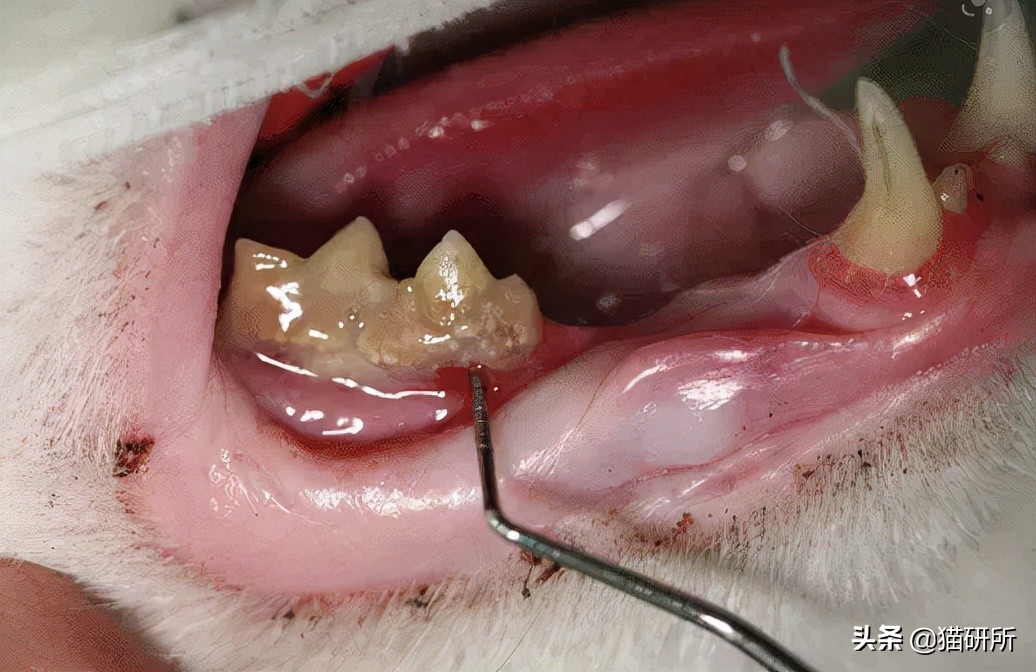

这时如果掰开猫咪嘴巴,能够看到猫咪牙齿周围软组织和骨组织的急性或慢性炎症反应,主要特点是牙齿松动、齿龈萎缩和口腔恶臭。

猫咪的牙结石、炎症、牙龈萎缩 图自:veterinarydentistry